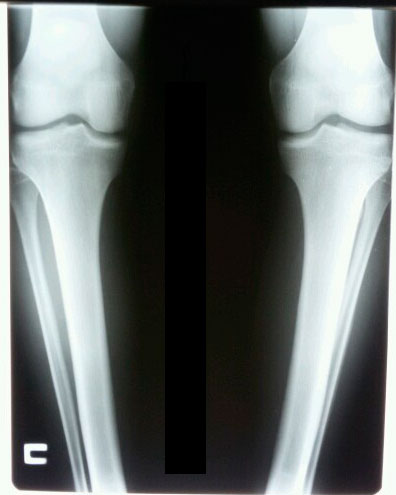

Дата операции 15.09.2015г.

Исходник.

РЕНТГЕН ДО ОПЕРАЦИИ